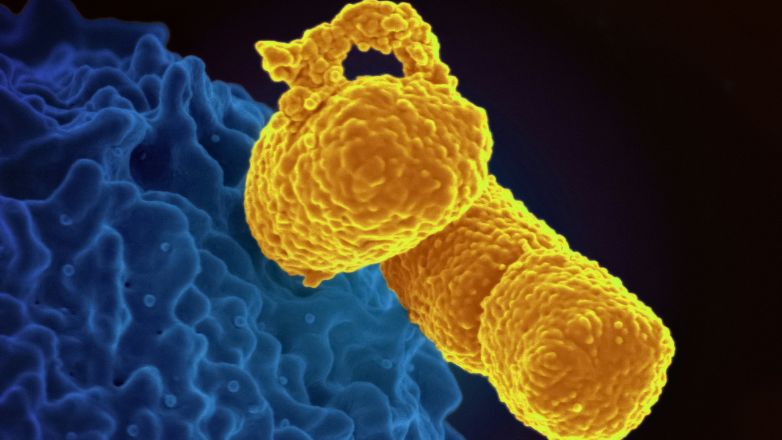

Klebsiella pneumoniae: To θανατηφόρο ανθεκτικό βακτήριο που εξαπλώνεται στην Ευρώπη

Μέσα σε τρία χρόνια, ο αριθμός των χωρών όπου έχει εντοπιστεί το ανθεκτικό στέλεχος του βακτηρίου Klebsiella pneumoniae αυξήθηκε από τις 4 στις 10